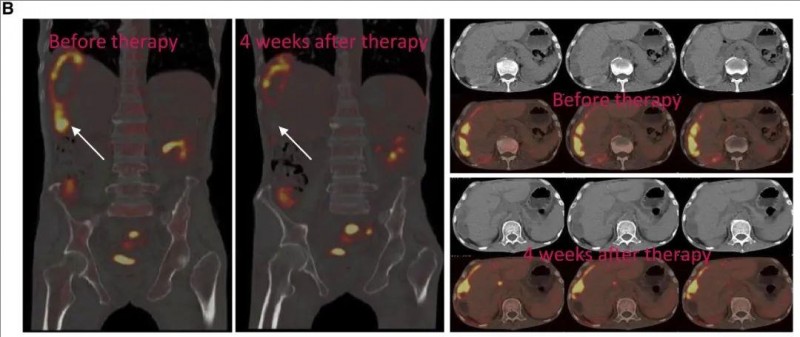

2、氟脱氧葡萄糖(FDG)PET/CT(正电子发射断层扫描-计算机断层扫描)成像显示:治疗完成后,肝段VI的最大标准化摄取值(SUVmax)从8.2,骤降至0.14(详见下图)。

▼癌症病变的PET-CT图像对比

▲图源“Mol Ther”,版权归原作者所有,如无意中侵犯了知识产权,请联系我们删除

注:

①左图(冠状PET-CT扫描):有证据表明S6中存在CAR-NK效应。

②右图(CT和PET/CT的横截面图像):显示CAR-NK治疗后S6的变化。